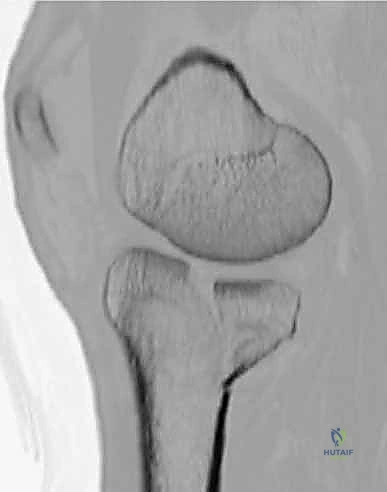

3. الأشعة المقطعية المحوسبة (CT Scan) - المعيار الذهبي

لا يمكن إجراء جراحة لكسر ثنائي اللقمة دون إجراء أشعة مقطعية (يفضل مع إعادة بناء ثلاثية الأبعاد 3D).

* توفر الأشعة المقطعية خريطة دقيقة لكل شظية عظمية.

* تحدد مقدار الانخساف في السطح المفصلي بالمليمتر.

* تكشف الشظايا المخفية، خاصة في الجزء الخلفي من الركبة (Posterior Coronally oriented fragments) والتي تتطلب خطة جراحية خاصة لتثبيتها.